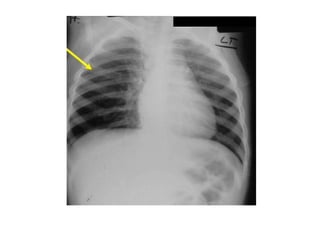

Case 2 16 month-old with wheezing

Imaging Findings A normal chest radiograph does not exclude an aspirated foreign body  Children will more often display signs of air-trapping while adults will more often show atelectasis  80% of aspirated foreign bodies will be non-opaque on conventional radiography

 Hyperinflation ofone lung or lobe may occur (obstructive emphysema)  Lobar or segmental atelectasis  Mediastinal shift  Pneumomediastinum  CT may demonstrate the foreign body or better show the narrowing of the bronchus